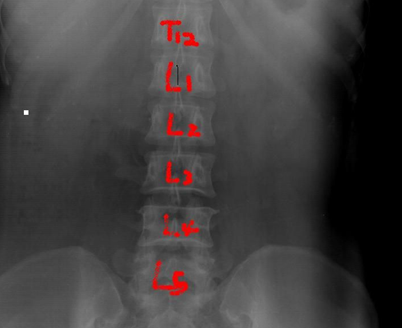

术前透视定位伤椎

正位:从头往尾,最后一节有肋骨的为T12,从尾往头,两髂嵴联线齐第四腰椎棘突。

“三长四翘五肥大”:一般L3横突较长,L4横突短而上翘,L5横突较肥大。

侧位:楔形变,双凹形变椎体为伤椎。

例:T12上肋骨没发育。

注意:L5骶化,S1腰化,T12无肋骨的特例。